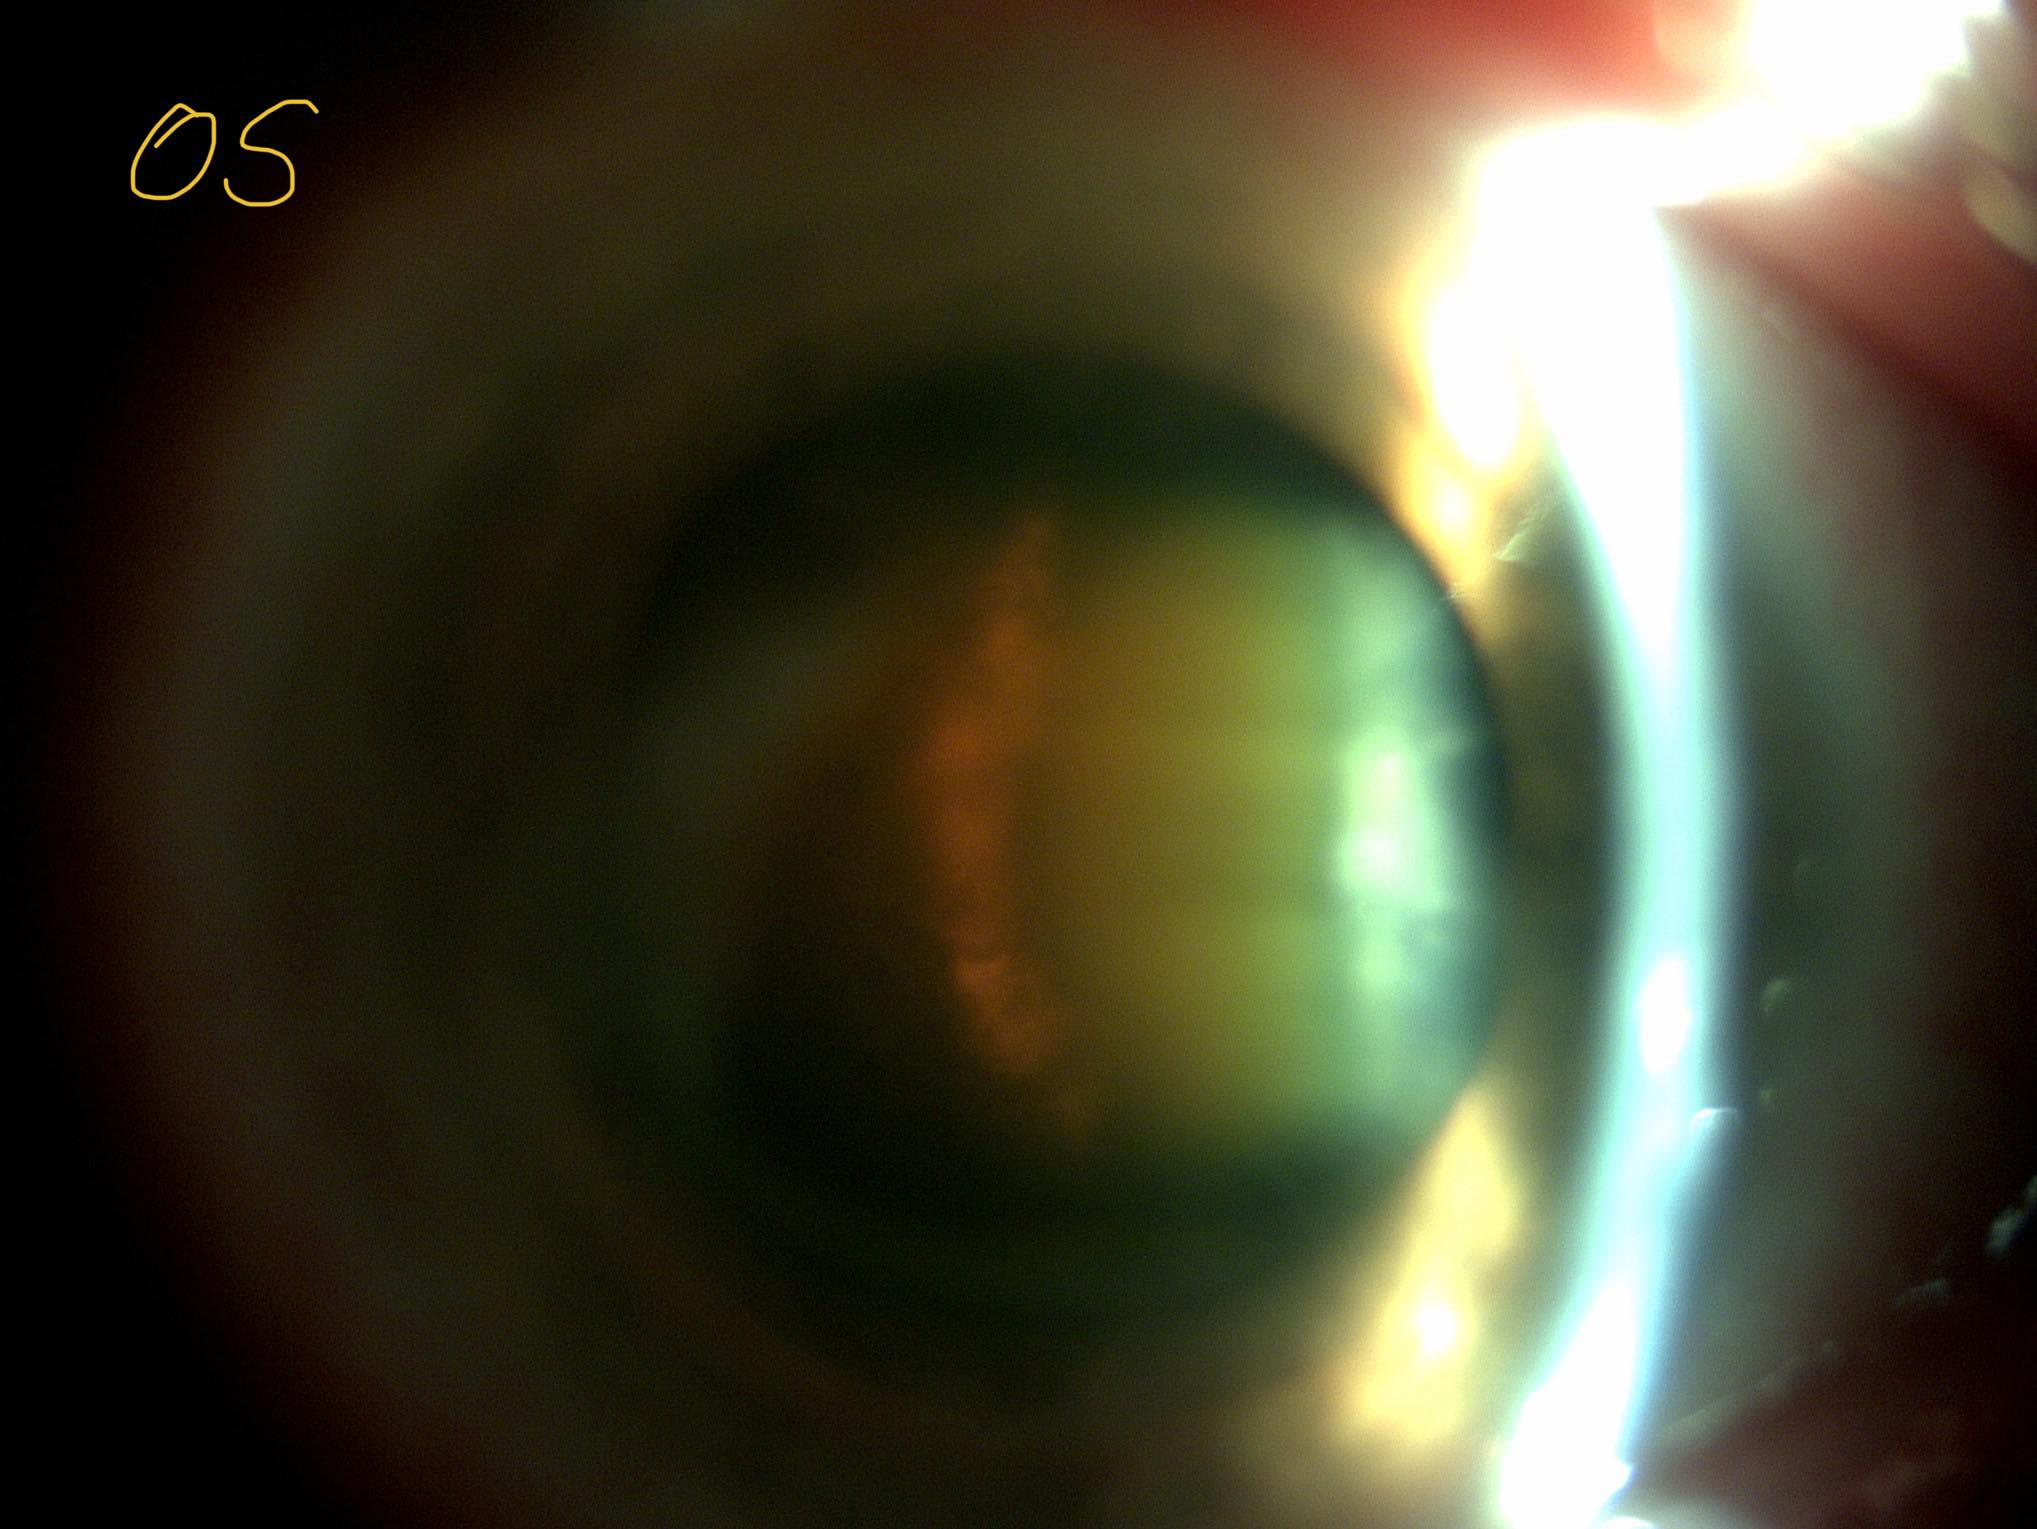

Această keratită a dus la subțierea extremă a corneei, cu deformarea ei neregulată, însoțită și de neo-vascularizație corneană periferică (apariția unor vase de sânge patologice, anormale, care nu-și au locul acolo), pe fond de sindrom de ochi uscat foarte sever (frecvent întâlnit în bolile autoimune).

Pe acest fond de cornee “anormală” a apărut și o cataractă foarte avansată, din cauza căreia pacienta noastră avea vederea foarte scăzută, sub 5% din standardul normal

Mai jos, câteva fotografii cu ambii ochi înainte de operație, urmate de două fotografii din timpul operației și ultimele două poze sunt ale ochiului operat, prima zi după operație.